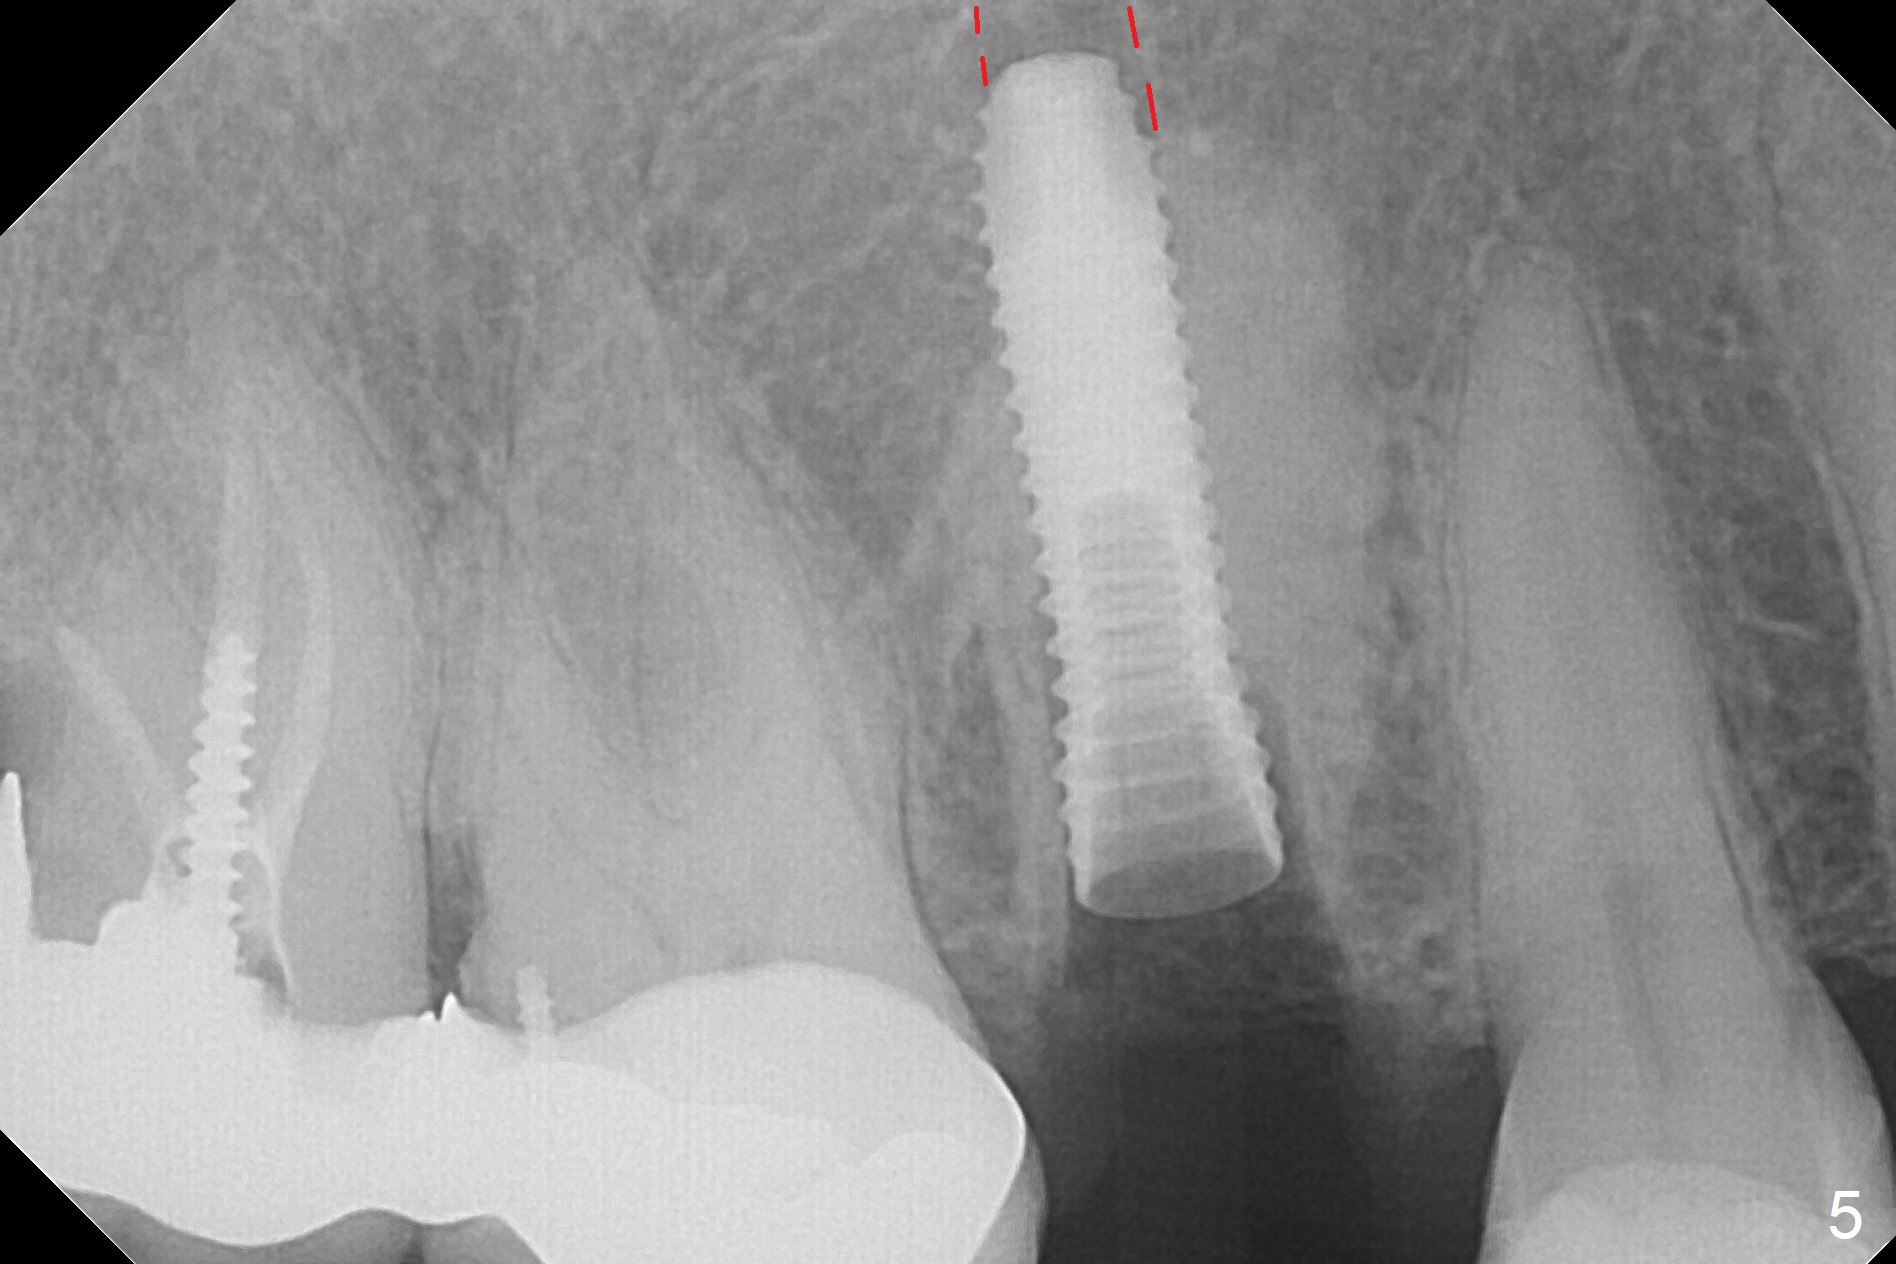

After extraction of the tooth #4 with palatally subgingival fracture (Fig.1 ^), white hard tissue is found in the socket, the density of which is hard (Fig.2 D). When osteotomy passes this portion of the bone (Fig.3 red dashed line), bone density feels reduced suddenly. The osteotomy is moved mesially slightly (Fig.4 (2.7 mm drill)). When a 3.8x15 mm dummy implant is placed with stability, there is an apical space (Fig.5 red dashed line). Therefore the final implant is longer (3.8x18 mm, <30 Ncm, Fig.6, 7). Vanilla graft is placed around the implant and a 4.5x4(4) mm abutment is placed immediately for an immediate provisional (Fig.8). Although the provisional easily dislodges in spite of remake, the implant seems osteointegrated with decreased space 4 months postop (Fig.9). The gingiva is healthy, although it covers the abutment margin partially. Gingivectomy appears necessary for impression.